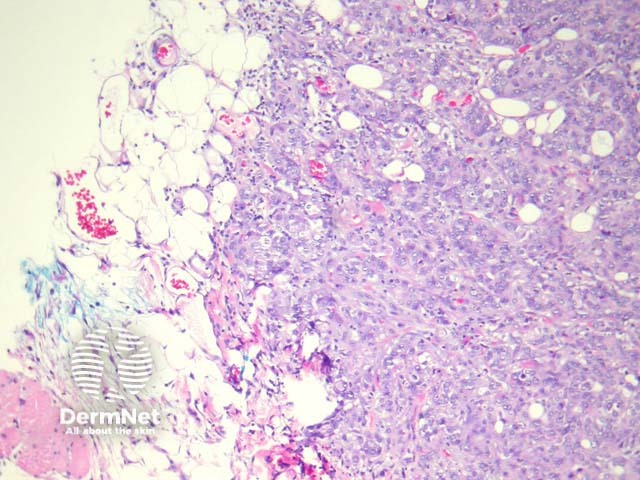

In sebaceous carcinoma, the tumour is generally dermally based with invasion into subcutis (figure 1) and native structures. Pagetoid invasion of the overlying epidermis may be seen. The tumour cells are basaloid with foci of sebocytic differentiation. Sebocytes are large cells with a multivacuolated clear cytoplasm (figure 2). Necrosis is common (figure 3, 4).

Figure 1